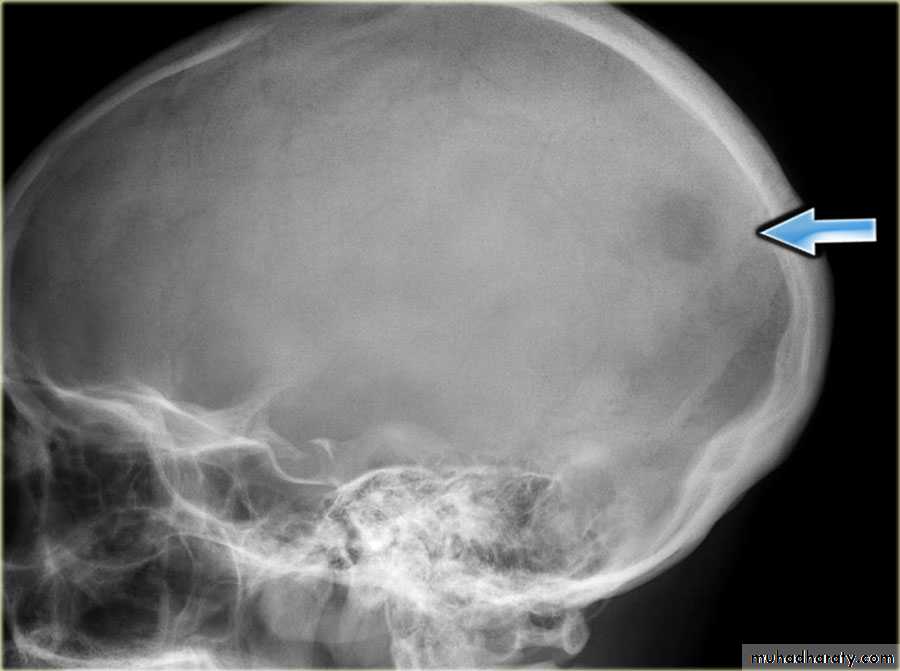

the initial radiological decision is usually to try &decide whether the solitary lesion is benign or its aggressive by looking for the following features on plain radiographs & CT :

1.Zone of transition

2.The adjacent cortex

3.Expansion

4.Periosteal reaction

7.Site:The site of a lesion is most important as certain lesions tend to occur at certain sites.Bone tumours